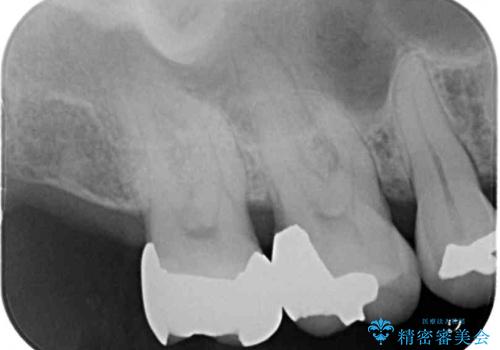

- 銀歯やインレーが外れたまま放置された奥歯の治療を希望して来院された患者様です。

咬合力が著しく強いため、欠損の多い歯はフルジルコニアクラウンへ、その他の虫歯はゴールドインレー(PGAインレー)にて修復することとしました。

来院時は全てセラミックでの治療を希望されていましたが、歯列や咬み合わせから咬合力による破損リスクが高いと判断されたため、ゴールドインレーを選択しました。